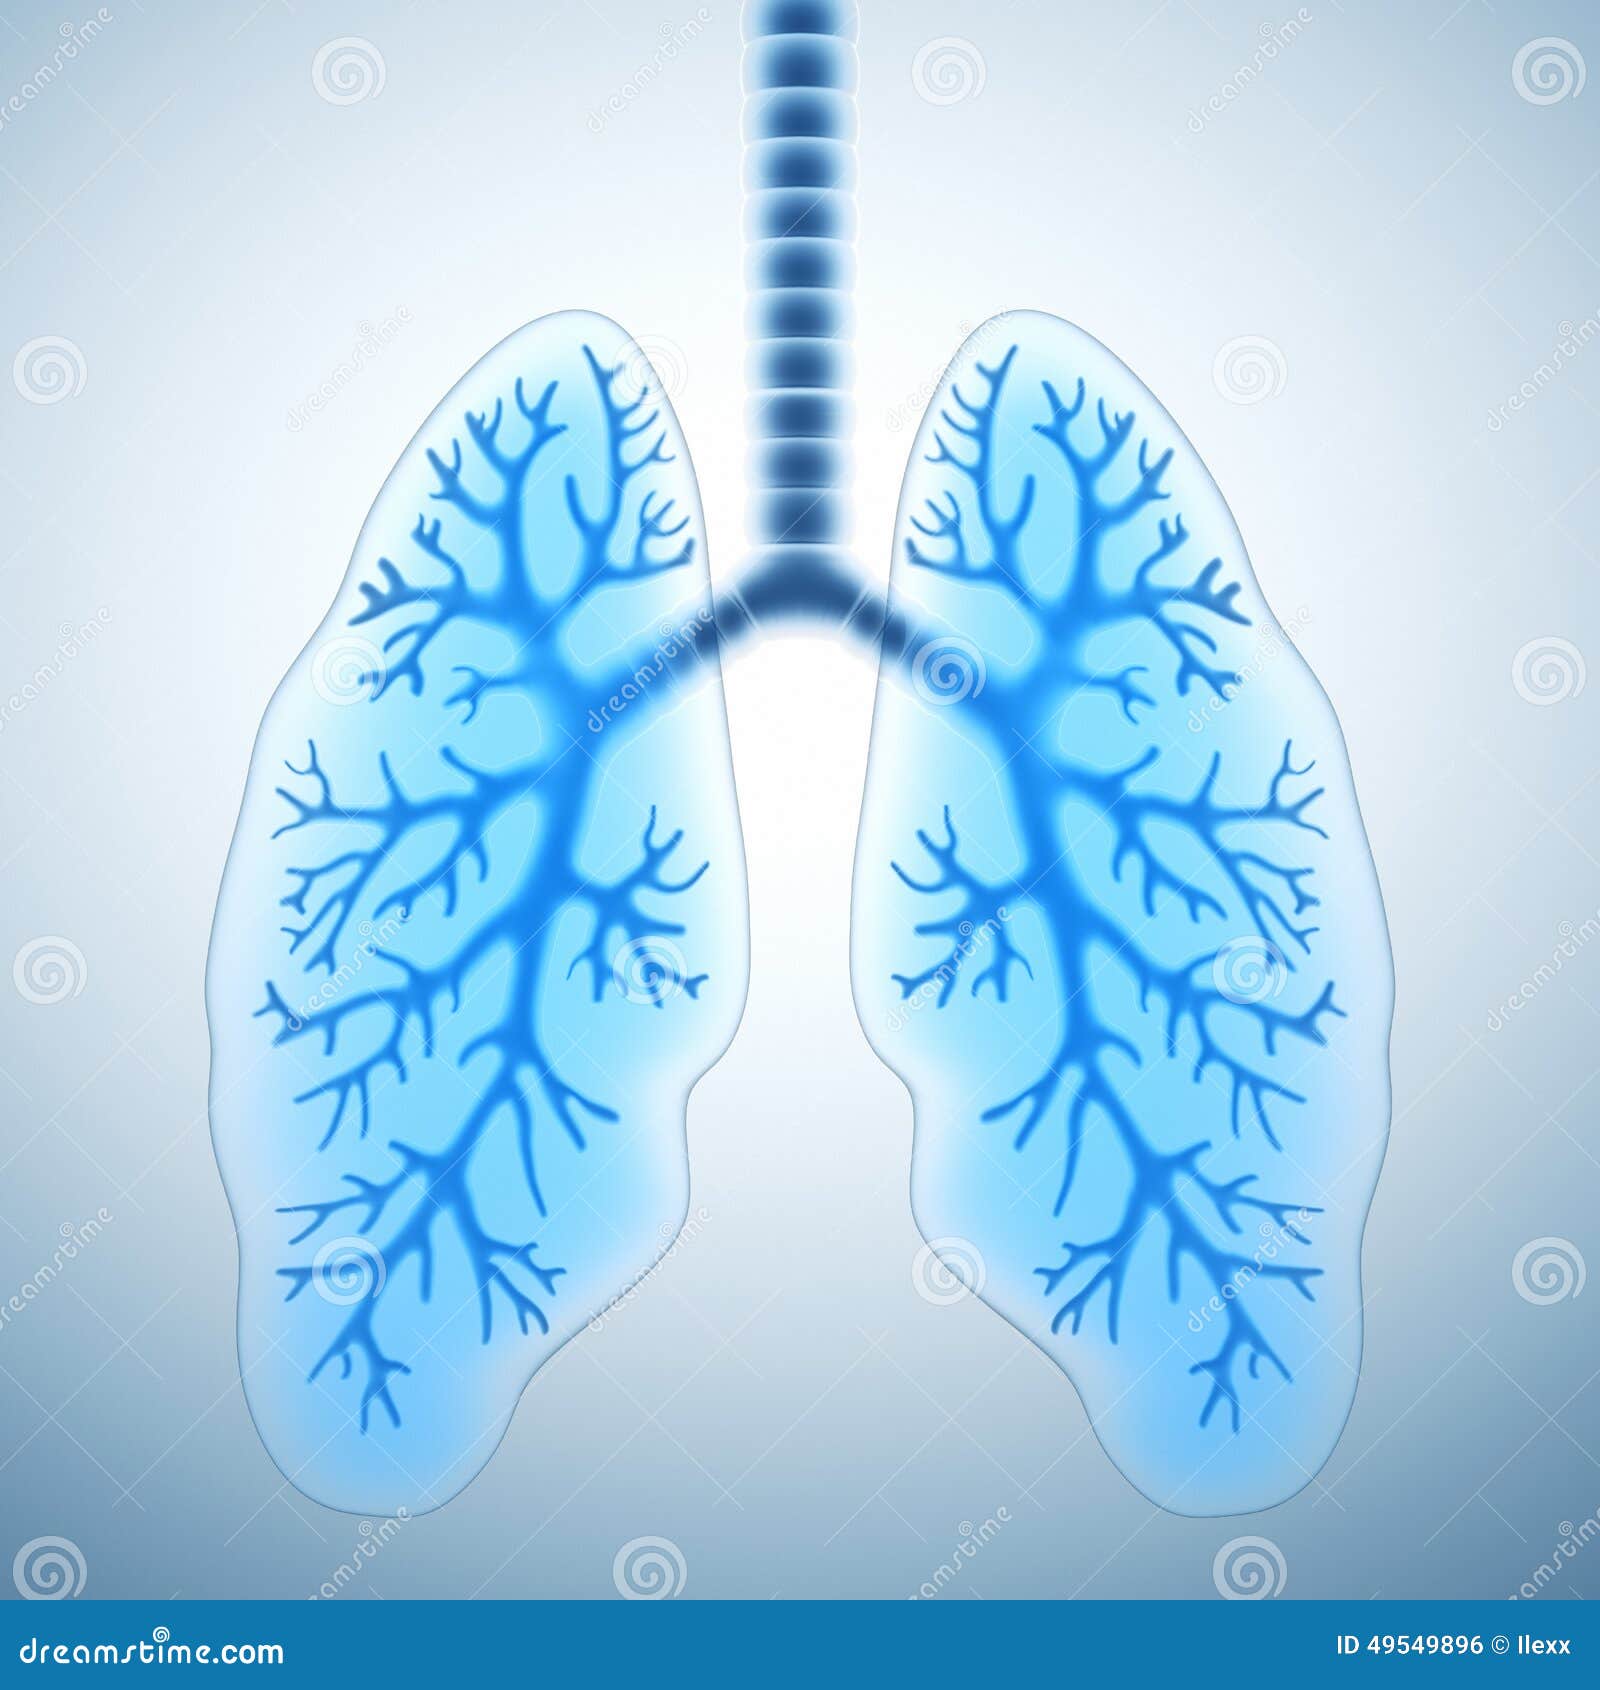

Здоровые Легкие Картинки

Здоровые Легкие Картинки 117 фото